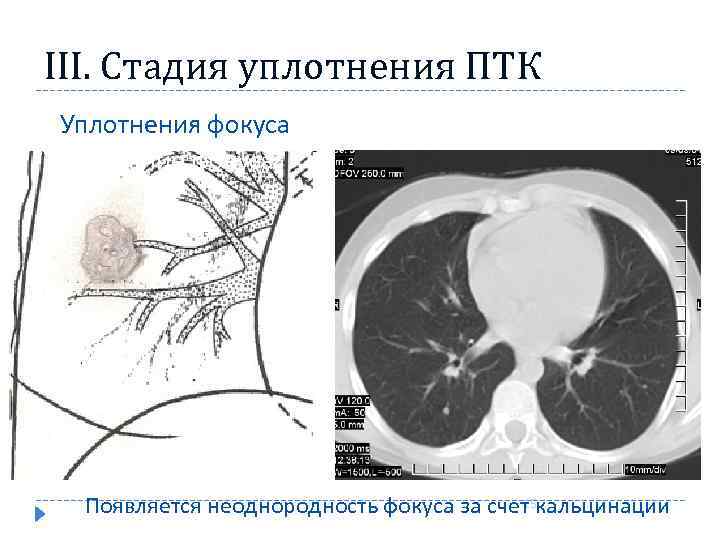

III. Стадия уплотнения ПТК Уплотнения фокуса Уплотнение фокуса 15 Появляется неоднородность фокуса за счет кальцинации

III. Стадия уплотнения ПТК Уплотнения фокуса Уплотнение фокуса 15 Появляется неоднородность фокуса за счет кальцинации

Рентгенологические признаки в стадию рассасывания и уплотнения ПТК постепенное исчезновение перифокальной инфильтрации в лёгочной ткани и перинодулярной инфильтрации в области корня лёгкого лёгочный компонент обычно представлен ограниченным затемнением или фокусом средней интенсивности, лимфатические узлы — расширением и деформацией корня лёгкого. размеры лёгочного компонента и поражённого корня лёгкого продолжают уменьшаться; постепенно в них обнаруживают признаки кальцинации 16

Рентгенологические признаки в стадию рассасывания и уплотнения ПТК постепенное исчезновение перифокальной инфильтрации в лёгочной ткани и перинодулярной инфильтрации в области корня лёгкого лёгочный компонент обычно представлен ограниченным затемнением или фокусом средней интенсивности, лимфатические узлы — расширением и деформацией корня лёгкого. размеры лёгочного компонента и поражённого корня лёгкого продолжают уменьшаться; постепенно в них обнаруживают признаки кальцинации 16